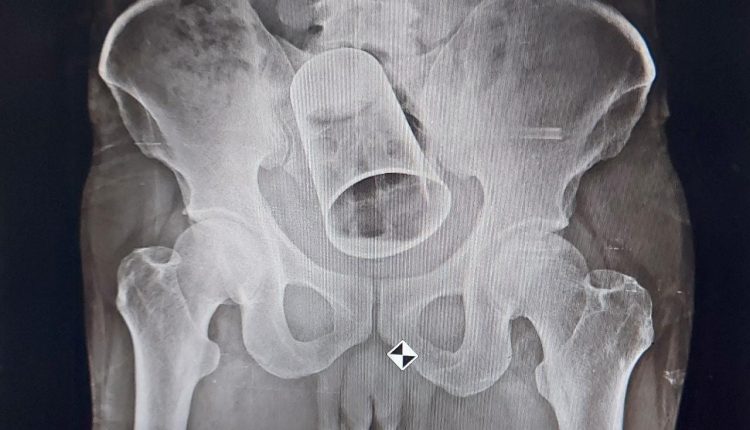

ଡାକ୍ତର ଏକ୍ସରେ କରିବା ପରେ ପେଟରେ ଏକ ଗ୍ଲାସ ଥିବା ଦେଖିବାକୁ ମିଳିଥିଲା । ଅଗଷ୍ଟ ୧୯ରେ ସର୍ଜରୀ ବିଭାଗର ଡାକ୍ତରମାନେ କୃଷ୍ଣଙ୍କ ଅନ୍ତଃନଳୀ କାଟି ଗ୍ଲାସଟିକୁ ବାହାର କରିଥିଲେ ।